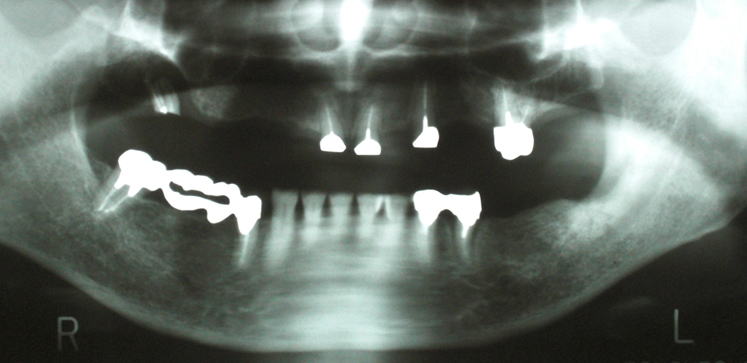

症例2

上顎にはマグネットタイプの入れ歯が入っていましたが、違和感も強く

漬物や繊維質の食品はとても食べられませんでした。

上顎に8本、下顎に3本のインプラントを植立しました。

見た目も自分歯と区別がつかずとてもきれいです。

漬物ももちろん食べられます。